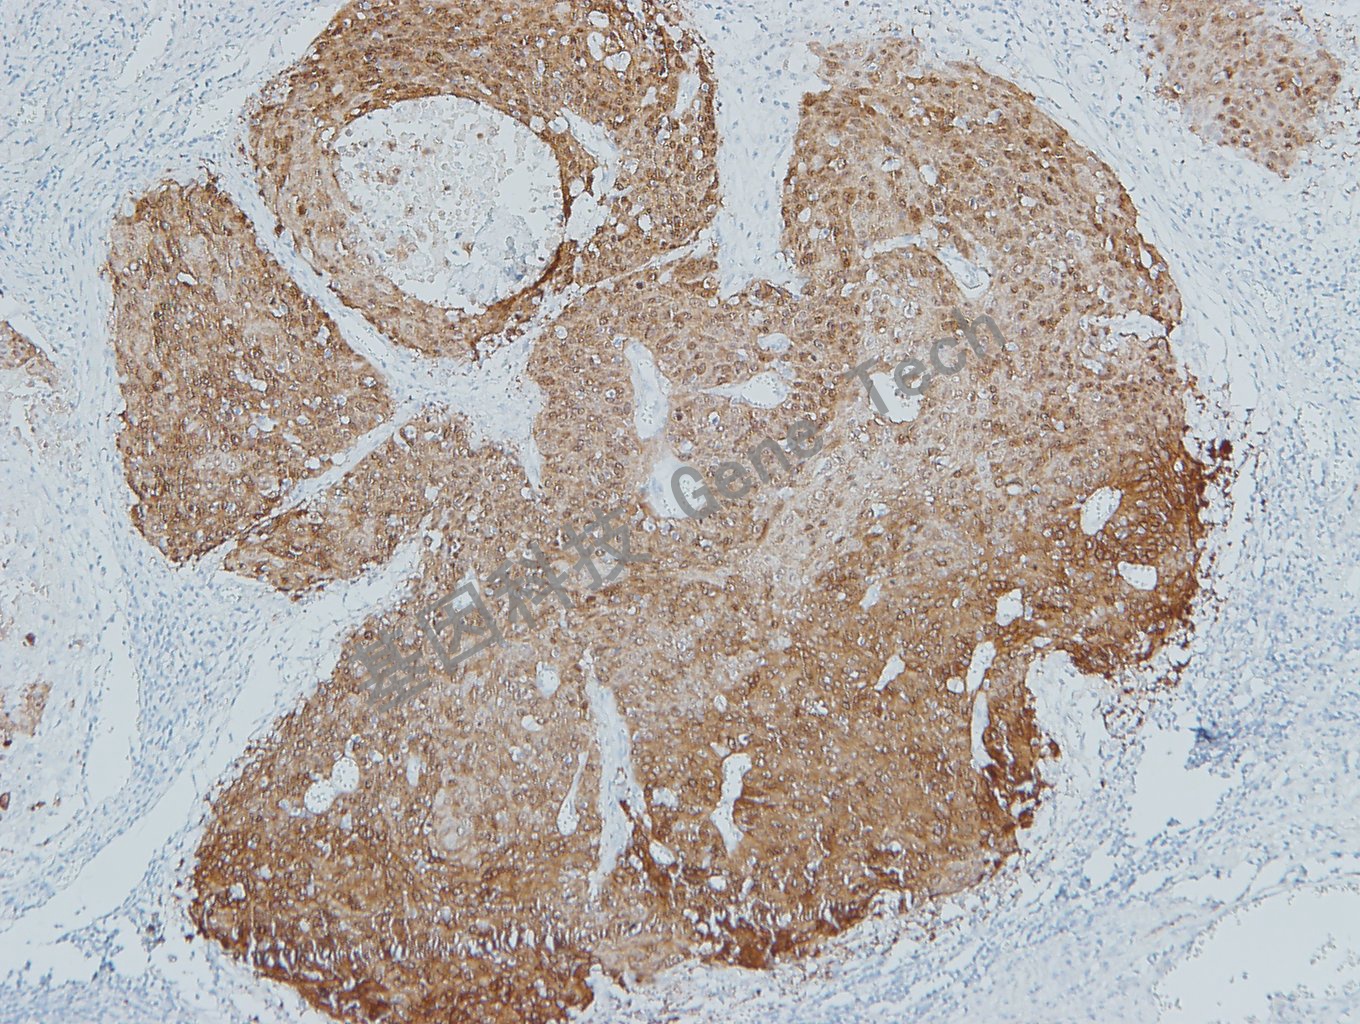

| 預(yù)處理:高pH熱修復(fù) | 陽性部位:細(xì)胞漿/細(xì)胞核 | 陽性對照:宮頸鱗癌 |

| 宮頸癌石蠟組織,用 p16(GT2330)染色,細(xì)胞漿/細(xì)胞核陽性,DAB 顯色。 | ||